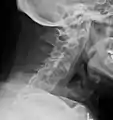

X-rays

The earliest changes demonstrable by plain X-ray shows erosions and sclerosis in sacroiliac joints. Progression of the erosions leads to widening of the joint space and bony sclerosis. X-ray spine can reveal squaring of vertebrae with bony spur formation called syndesmophyte. This causes the bamboo spine appearance. A drawback of X-ray diagnosis is the signs and symptoms of AS have usually been established as long as 7–10 years prior to X-ray-evident changes occurring on a plain film X-ray, which means a delay of as long as 10 years before adequate therapies can be introduced.[24]

Options for earlier diagnosis are tomography and MRI of the sacroiliac joints, but the reliability of these tests is still unclear.